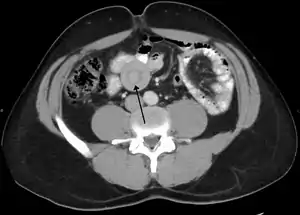

| نمای یک درهم روی روده در سی تی اسکن | |